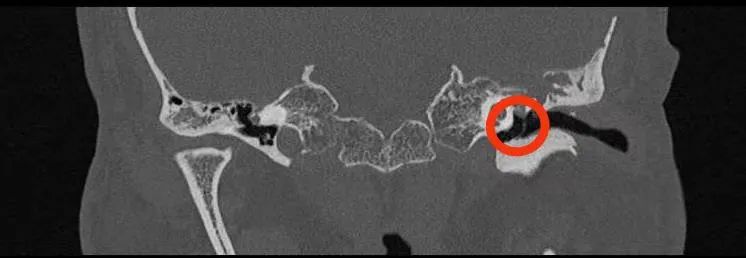

▲术前鼓室积液,示脑脊液耳漏。

▲术后1月复查鼓室积液消失,示脑脊液耳漏修补成功。

术后无不适症状,术后复查听力较术前明显提高,复查CT显示脑脊液漏修补成功,鼓室积液消失,鼻腔再也不滴水了,困扰患者40年的头痛的问题终于得到解决。